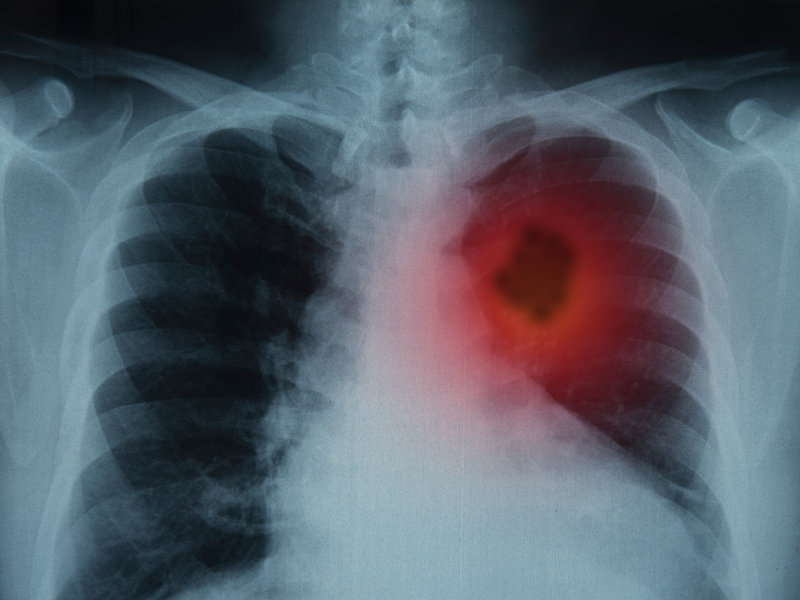

1、頻繁乾咳

咳嗽是非常常見的症狀,並不是所有咳嗽都與肺癌有關。但若本身屬於高危人群,且咳嗽遲遲不見好轉,並伴有痰中帶血、聲音嘶啞,乾咳持續,且夜晚有加重症狀,甚至會影響睡眠,就要警惕是肺部腫瘤引起。